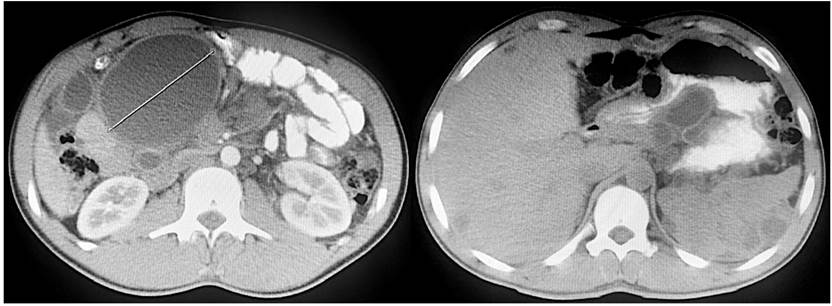

Se le realizó una tomografía de abdomen y pelvis simple y contrastada, donde se documentó hepatoesplenomegalia leve, quistes simples intrahepáticos y esplénicos de distribución difusa, quistes mesentéricos, también en forma difusa, dilatación de asas intestinales con importante distensión del duodeno (Figura 2). Se valoró en junta quirúrgica de Cirugía General, donde se consideró que, por hallazgos en estudios imagenológicos, con etiología no clara, se debía descartar colecciones residuales de procedimientos quirúrgicos previos y se debía llevar a laparotomía exploratoria, con resección de quistes para realizar y estudio patológico para definir la etiología y conducta final.

Figura 2 Tomografía abdominal y pélvica simple y contrastada. Corte axial que muestra numerosas lesiones redondeadas de contenido líquido, encapsuladas y distribuidas en la raíz del mesenterio, hígado, bazo y peritoneo.